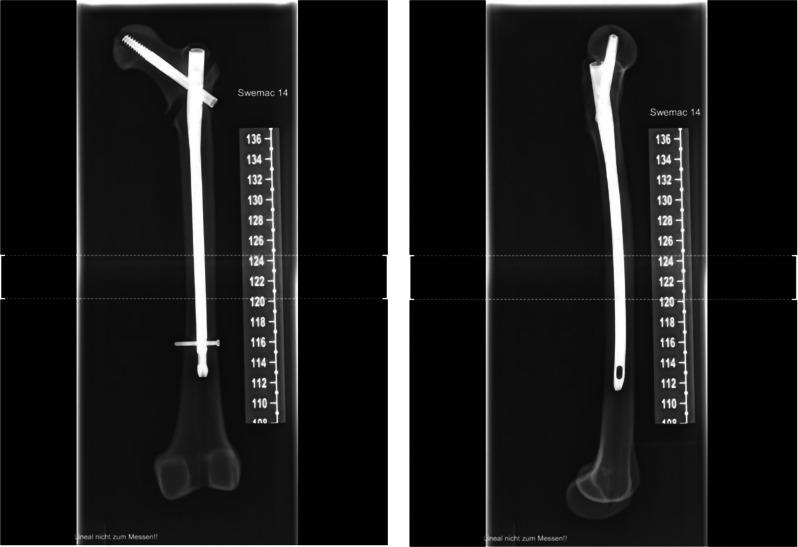

Complex fractures of the trochanteric region, as well as fractures located in the directly subtrochanteric region, are controversially discussed around the world regarding the nail type to be used. A long nail is recommended by manufacturers but requires longer surgical and fluoroscopy times. A possible solution could be a nail with an appropriate length which can be locked in a minimally invasive manner by the main aiming device. We aimed to determine if such a nail model (DCN SL nail, SWEMAC, Linköping, Sweden) offers similar structural stability on biomechanical testing on artificial bone as a standard long nail when used to treat complex trochanteric fractures and compared it to long nails usually used in this setting.

An osteoporotic bone model was chosen. The Swemac Hansson DCN Nail System was used as osteosynthesis material. Two types of nails were chosen: a superior lock nail which can be implanted with a singular targeting device, and a long nail with distal locking using free-hand technique. AO31A2.2 fractures were simulated in a standardised manner. Axial height of the construct, varus collapse, and rotational deformity directly after nail insertion were simulated. A Universal Testing Machine was used. Measurements were made with a stereo-optic tracking system.

在全球范围内,对于转子间区域的复杂骨折以及直接转子下区域的骨折,关于使用何种类型的髓内钉存在争议。制造商推荐使用长钉,但这需要更长的手术和透视时间。一种可能的解决方案是使用一种适当长度的钉,该钉可以通过主要瞄准装置以微创方式锁定。我们旨在确定这种钉模型(DCN SL 钉,SWEMAC,林雪平,瑞典)在用于治疗复杂转子间骨折的人工骨生物力学测试中是否与标准长钉一样具有相似的结构稳定性,并将其与通常在此环境中使用的长钉进行比较。

选择骨质疏松骨模型。使用 Swemac Hansson DCN 钉系统作为骨合成材料。选择了两种类型的钉子:一种是可以通过单个瞄准装置植入的上锁定钉子,另一种是使用徒手技术进行远端锁定的长钉子。以标准化的方式模拟 AO31A2.2 骨折。模拟直接插入钉子后构建体的轴向高度,内翻塌陷和旋转变形。使用万能试验机。使用立体光学跟踪系统进行测量。